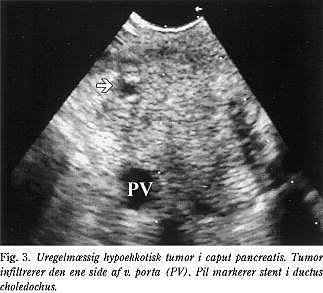

Cancer pancreatis

EUS og EUS-FNA er vigtige undersøgelsesmetoder ved diagnostik af suspekte forandringer i pancreas og til stadievurdering af patienter med erkendt pancreascancer. Ved EUS kan man erkende forandringer i pancreas, der ikke har været set ved andre diagnostiske modaliteter (f.eks. CT eller ekstern UL), og vha. EUS-FNA kan diagnosen bekræftes (11, 12). Ved stadiebedømmelse af cancer pancreatis er EUS CT, UL og angiografi overlegen (Fig. 3 ) (13, 14), idet EUS også kan under- og overvurdere T-stadiet (15, 16). Den kliniske betydning af dette er dog relativ beskeden, da EUS hos 93% giver korrekt udsagn om, hvorvidt tumoren kan fjernes kirurgisk. Tilbage bliver der en gruppe patienter, hvor det vil være nødvendigt med supplerende undersøgelser, hvis man, inden der planlægges kurativt indgreb, ønsker at øge sikkerheden for, at tumoren faktisk er resektabel. Laparoskopi og LUS er velegne de til yderligere at nedsætte antallet af unødvendige eksplorative indgreb (17, 18), men da EUS er den billigste og mindst invasive procedure, bør den anvendes som den første undersøgelse til præoperativ stadiebedømmelse og resektabilitetsvurdering ved cancer pancreatis (8).